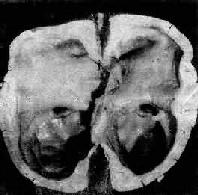

<a href=海马钩回疝"/>

图16-7 海马钩回疝

海马回内侧肿胀有深切迹(箭头),中脑右移变形,中脑右大脑脚受压,局部坏死出血(Kemohan切迹)